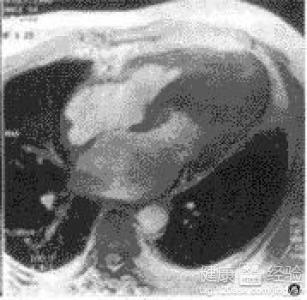

擴張性心肌病是一種嚴(yán)重的心臟疾病,但“心之港灣”為你帶來希望,這里的專家團隊一直在深入研究擴張性心肌病的最新治療方法,并深知每位患者都渴望得到最佳的治療和關(guān)懷,他們努力不懈,為患者帶來生機和新生。